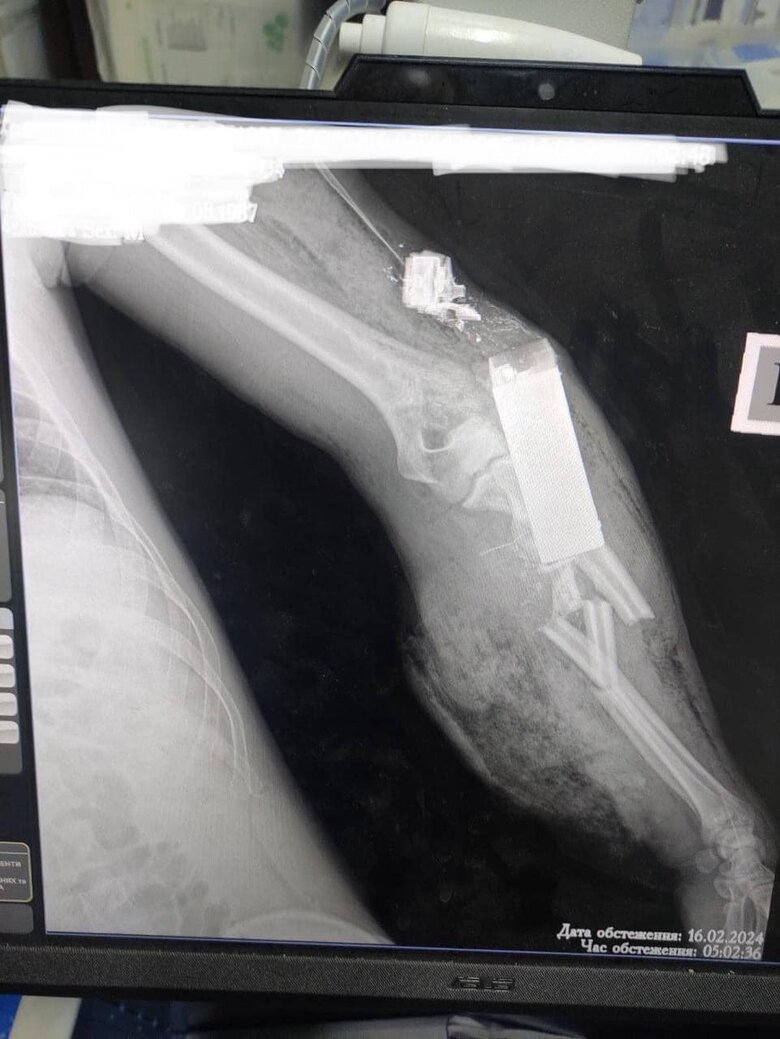

Doctors remove VOG-17 grenade warhead from wounded Ukrainian soldier’s arm. PHOTO

Military doctors removed the warhead of a VOG-17 (grenade launcher fragmentation round -ed. note) grenade from the wounded Ukrainian defender’s arm, saving not only his life but also his limb.